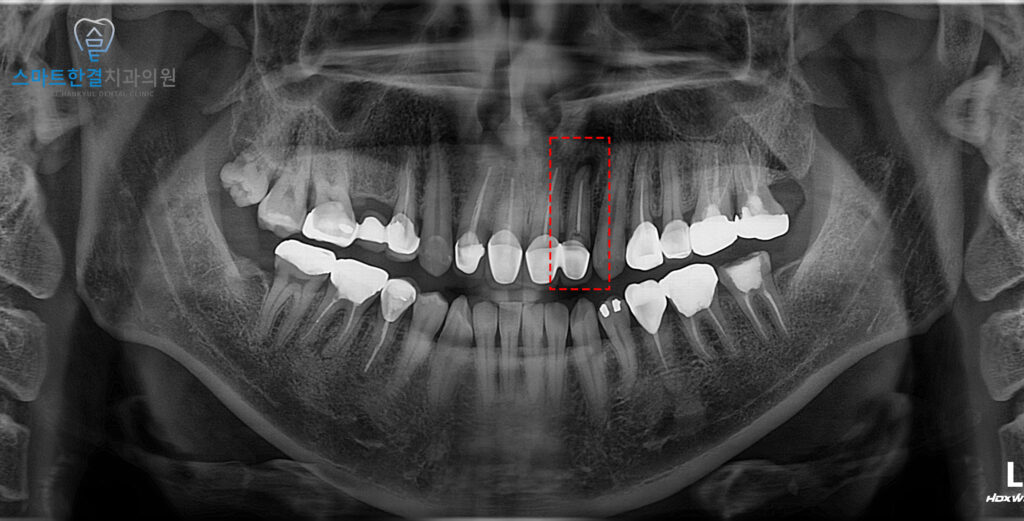

파노라마 사진을 확인해 보니,

왼쪽 위 앞니에 뿌리 끝으로 염증이

잡혀있는것을 확인할 수 있었어요.

신경치료를 진행한 치아의

근관 내 오염으로 인해

뿌리 끝에 감염이 발생하고,

그로 인해 염증이 발생한 상태였는데요.